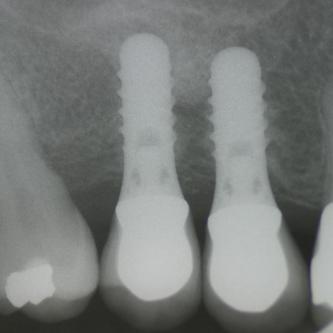

Exemple 9: Un cas complexe, 3 implants on été mis au niveau de la mandibule.

Exemple 9: Une barre est vissée sur ces 3 implants.

Exemple 12: Les moignons vissés sur les implants 6 mois plus tard.

Exemple 12: Les couronnes en place.